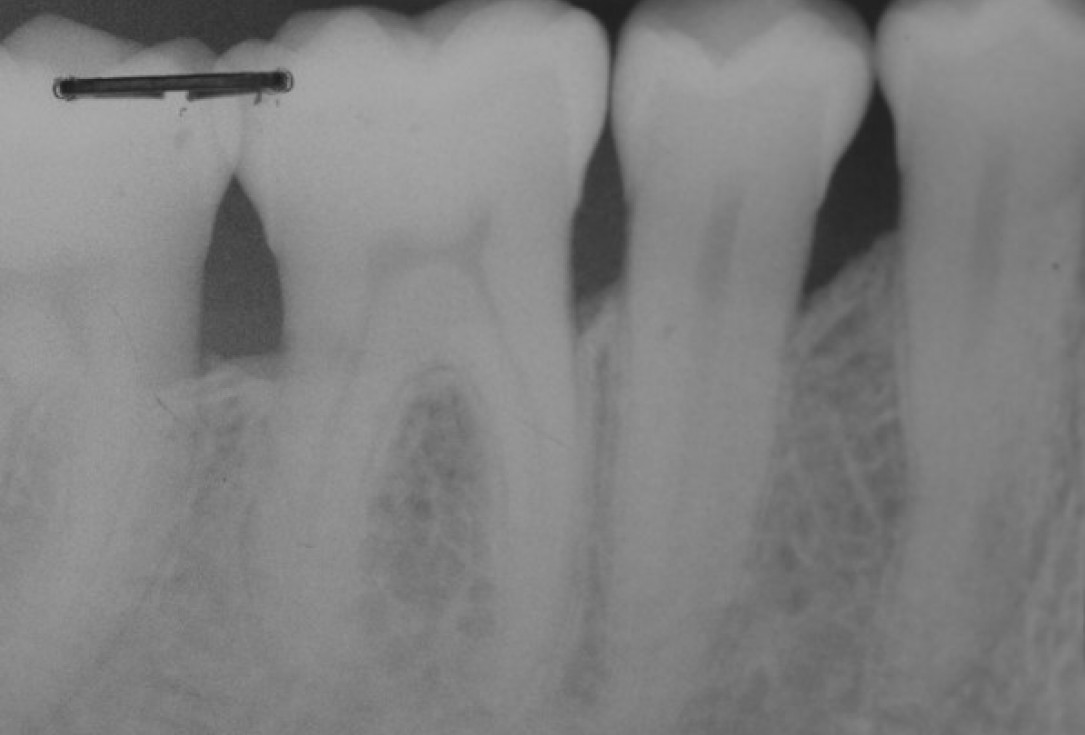

18/22 - Radiographic follow up 12 months post-operative. The radiograph demonstrates a complete defect fill and a stable result.

Deep intrabony defects treated using Straumann® Emdogain® - Dr. M. Stefanini